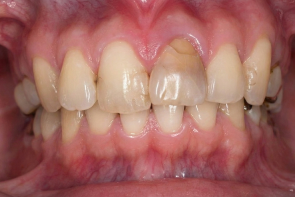

米国の技術×専属技工士×精密機器のフル活用で「短期治療」を実現!

米国の先端治療を安価で

インプラント、マウスピース矯正、小児矯正の歯医者なら「ALBA歯科&矯正歯科」。東京・神奈川・海外を中心に26医院を展開する当グループの専門治療をご案内します。年間1,000症例以上の「世界レベル」オペを実施しているインプラント治療では最安で税込99,800円~の低価格を実現。目立たずメンテナンスも容易と好評の透明なマウスピース矯正は月3,300円からご提供が可能です。重度の歯周病でも徹底的な検査と滅菌で再発を防止し、包括治療で早期解決します。低価格・低リスクの「小児専門」矯正治療を実現、通常100万円ほどかかるワイヤー矯正と比べ、半額程度の費用で矯正治療がおこなえます。年中無休で土・日・祝日も診療中。朝10時台から夜20時(鶴ヶ峰院、上永谷院は19時)まで受診可能。

年間1,000症例以上の 「世界レベル」オペ実施

最安で税込99,800円~の低価格を実現